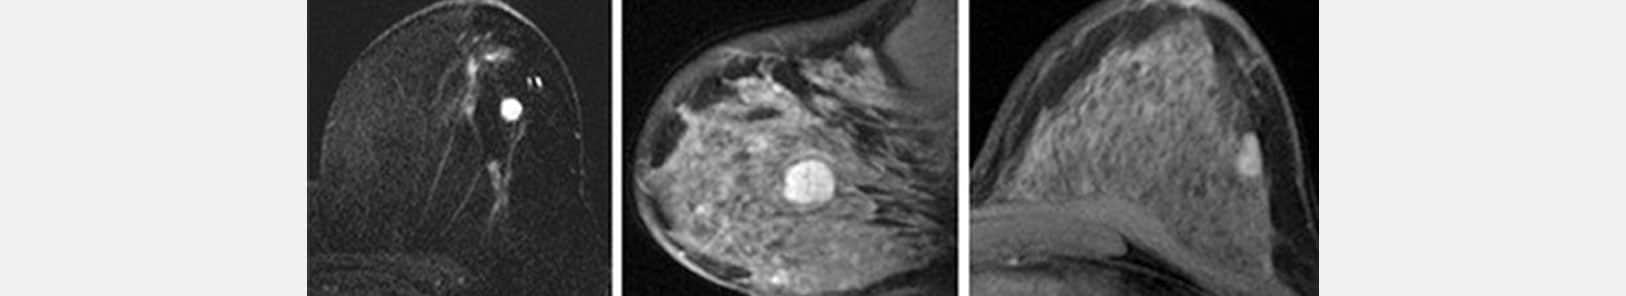

МРТ является дополнительным исследованием.

МРТне заменяет маммографию или УЗИ. Оно не является систематическим обследованием ни для скрининга, ни для диагностики рака молочной железы.

Это дополнительное обследование, которое иногда назначает врач:

- В рамках скрининга у некоторых пациентов с высоким риском развития рака (генетическая мутация).

- При подозрении на онкологию помочь в постановке диагноза, когда стандартная визуализация не позволяет сделать вывод с уверенностью.

- В случае подтвержденного рака лучше уточнить степень поражения.

- Во время лечения, особенно в случае предоперационной химиотерапии.

Женщинам в пременопаузе МРТ в идеале следует проводить между 8-м и 12-м днем цикла.

Женщинам в постменопаузе, получающим заместительную гормональную терапию, рекомендуется прекратить это лечение за 6–8 недель до обследования.